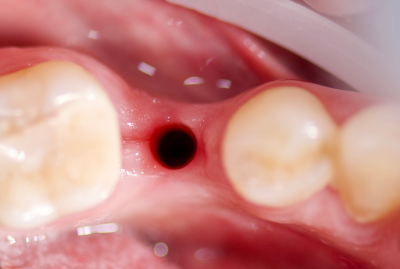

Восстановление утраченного зуба 45 у возрастной пациентки.

✔️ В мягкую кость области зуба 45, удалённого незадолго до обращения, установлен агрессивный корневидный имплант Vega+

✔️ Через 4 месяца проведено протезирование керамической коронкой с трансокклюзионной фиксацией.